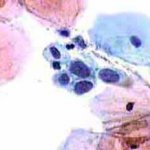

Δυσπλασίες τραχήλου μήτρας σοβαρού βαθμού (CIN III)

Ασυμπτωματική ασθενής 39 ετών. PH κόλπου 4,4. Κολποσκόπιση:

Στην δοκιμασία οξικού οξέως και στην δοκιμασία Lugol, αρνητική περιοχή, τόσο στο πρόσθιο, όσο και στο οπίσθιο χείλος του τραχήλου, σε ακτίνα 3-4 χιλ. και πλάτος περίπου 5 χιλ., με εικόνα διακριτικού επίπεδου μωσαϊκού.